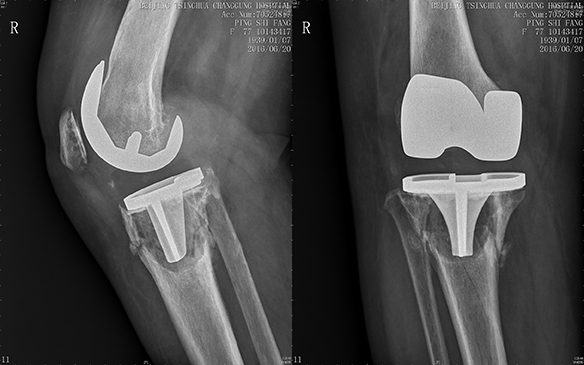

手术中,蔡谞教授在保留最大骨量的同时安全的将松动的假体和衬垫取出,同时进行彻底清创,将感染的风险降到最低,在面对几乎已经完全消失的胫骨平台,蔡谞教授选择使用胫骨锥形填充块(CONE)起到支撑作用,同时在填充块内进行植骨以促进骨长入。同时在填充块和胫骨假体之间填充骨片,撑起胫骨假体。手术共进行了3个小时左右,在关节中心团队以及手术室麻醉相关科室的合作下,手术很成功。严重的骨缺损得到了良好的处理,翻修假体位置良好,患者术后第3天即可下地。

图为胫骨锥形填充块内填充异体骨